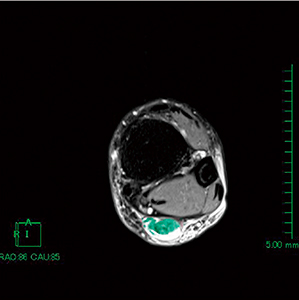

図3 アキレス腱部選択画像

計測するスライスを決め,アキレス腱部(緑色)を目視にて選択していく。